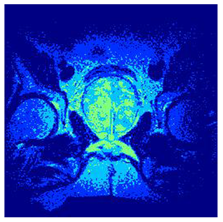

In this subsection, we will discuss the experiment designed to evaluate the performance of EO with cross-entropy for the segmentation of prostate MRI images. To this end, we use a group of reference images formed by a set of six prostate MRI images; see Figure 4. All the images from the group were extracted from the Ferenc Jolesz National Center for Image-Guided Therapy, Harvard Medical School, or Brigham Health Hospital datasets with no additional preprocessing [50]. Prostate MRI images are primarily used for disease diagnosis or to establish treatment for prostate-related diseases such as prostatitis, benign prostatic hyperplasia (BPH), and prostate cancer, among other diseases or medical conditions. In the context of this article, the images were used to test the efficiency of the equilibrium optimizing algorithm and compare it with the other six chosen algorithms. The segmentation of MRIs is carried out over four different thresholds levels: = 3, 4, 5, and 8. Due to the nature of the images, there was a limited number of different tissues in the images; thus, there was no point in evaluating a larger number of .

Figure 4.

Eleven transaxial-cut prostate MRI images. This figure presents a set of eleven transaxial-cut magnetic resonance (MR) images of the prostate. These images serve as the input dataset for evaluating the segmentation performance of the proposed algorithm.

Table 5 presents the segmentation of the MRIs using EO for a qualitative inspection. From Figure 5, it is clear that two lumps in the prostate have been highlighted by the thresholding process. Prostatic MRIs present noisy conditions, which makes it difficult to visualize the thresholding with the naked eye, so in Figure 5 we present the thresholded image as well as the histogram with the values of the thresholds generated by the EO. It can be observed in the histogram that the thresholds present an adequate distribution, even though this particular image has impulsive noise and a simple shape. Our findings indicate that four thresholds are typically sufficient for this application, which corresponds to identifying five different tissue types in the image. A smaller threshold value may result in a lack of sufficient contrast to highlight relevant anatomical structures, such as the prostate capsule. In contrast, a higher number of thresholds may lead to the incorrect differentiation of anatomical regions that should be connected.

Table 5.

Segmentation of transaxial-cut prostate MRI images Using EO and cross-entropy. This table presents the segmentation results of transaxial-cut prostate MRI images using the equilibrium optimizer (EO) and cross-entropy. Each row corresponds to a distinct MRI image, while the columns nt represent the number of thresholds applied during segmentation. The results illustrate the performance of the EO algorithm across different threshold levels for each image.